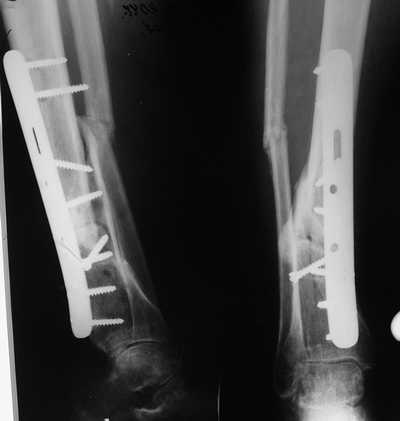

Male 54 years old, diabetic, blind in both eyes, with infected (MRSA) non union distal tibia after fracture 8 month ago. In acute phase treated by ORIF with LCP tibia and fibula. Treatment complicated by infection and after 6 month hardware was removed and treatment continued by cast fixation. You can see malposition of fragments In this stage beginning treated by Ilizarov fixation with use Hexapod system, allows anatomical position of fragments and you see signs of union.